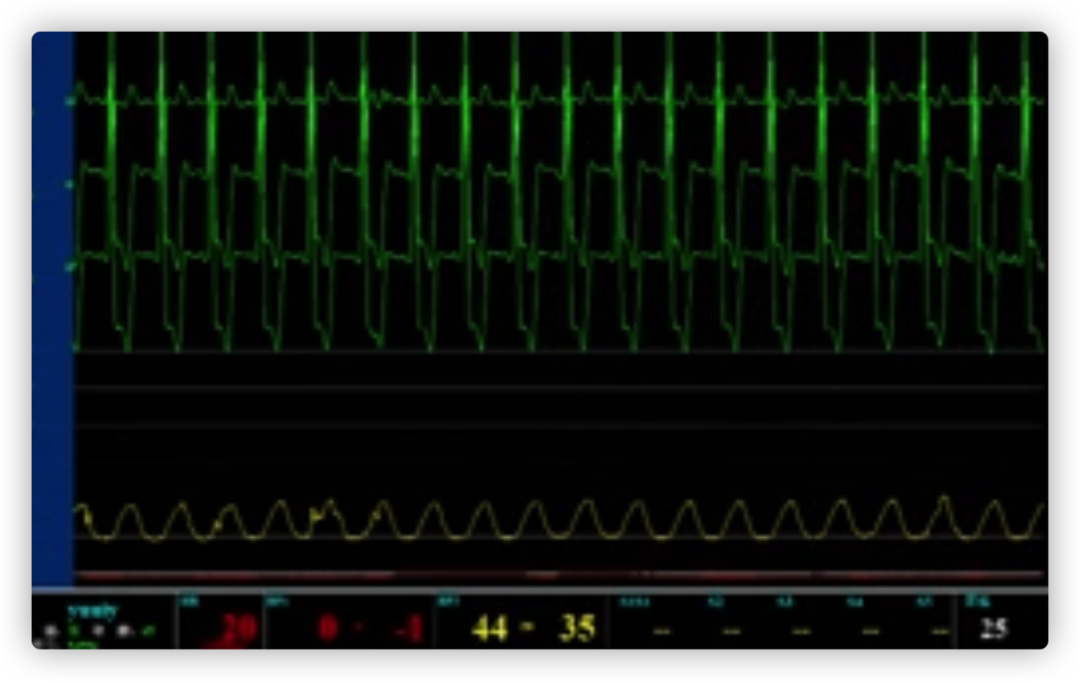

ECG术后即刻

ECG出院时